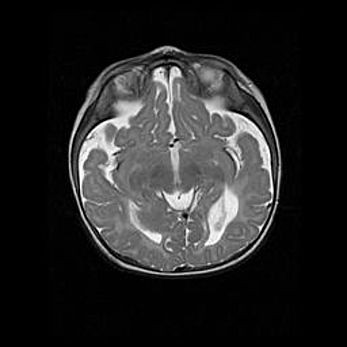

Церебральная ишемия II.

Возраст: 5 дней

Вес: 3400 г

Пол: женский

Окружность головы: 35 см

Срок гестации: 39 недель

Церебральная ишемия – это заболевание, характеризующееся недостаточностью (гипоксией) либо полным прекращением (аноксией) снабжения мозга кислородом по причине закупорки одного или нескольких сосудов. Это приводит к  что метаболическим расстройствам различной степени тяжести в тканях головного мозга, развитию коагуляционных некрозов и гибели нейронов.